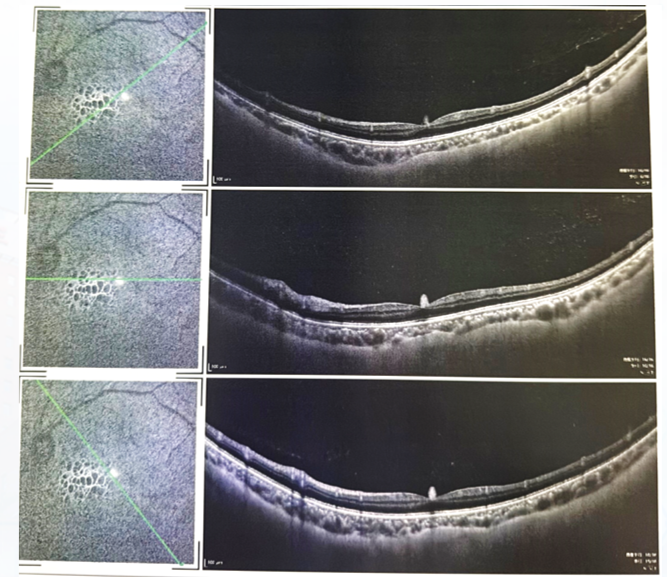

OCT:左眼玻璃体多发点状高反射,黄斑区视网膜结构尚完整(图3)。右眼黄斑上方可见两处视网膜色素上皮脱离(PED),余黄斑区视网膜结构尚完整(图4)。

图片

图3. 左眼外院OCT检查结果

图4. 双眼OCT检查结果